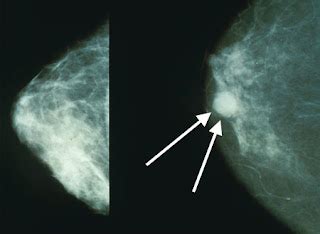

Warna pink pada pita kesadaran kanker payudara melambangkan harapan dan dukungan yang tidak pernah padam. Ini adalah pengingat bahwa kanker payudara dapat disembuhkan jika terdeteksi dan ditangani sejak dini. Warna pink juga mewakili kekuatan dan ketahanan para pejuang kanker payudara, yang mampu menghadapi penyakit ini dengan penuh keberanian dan optimisme.